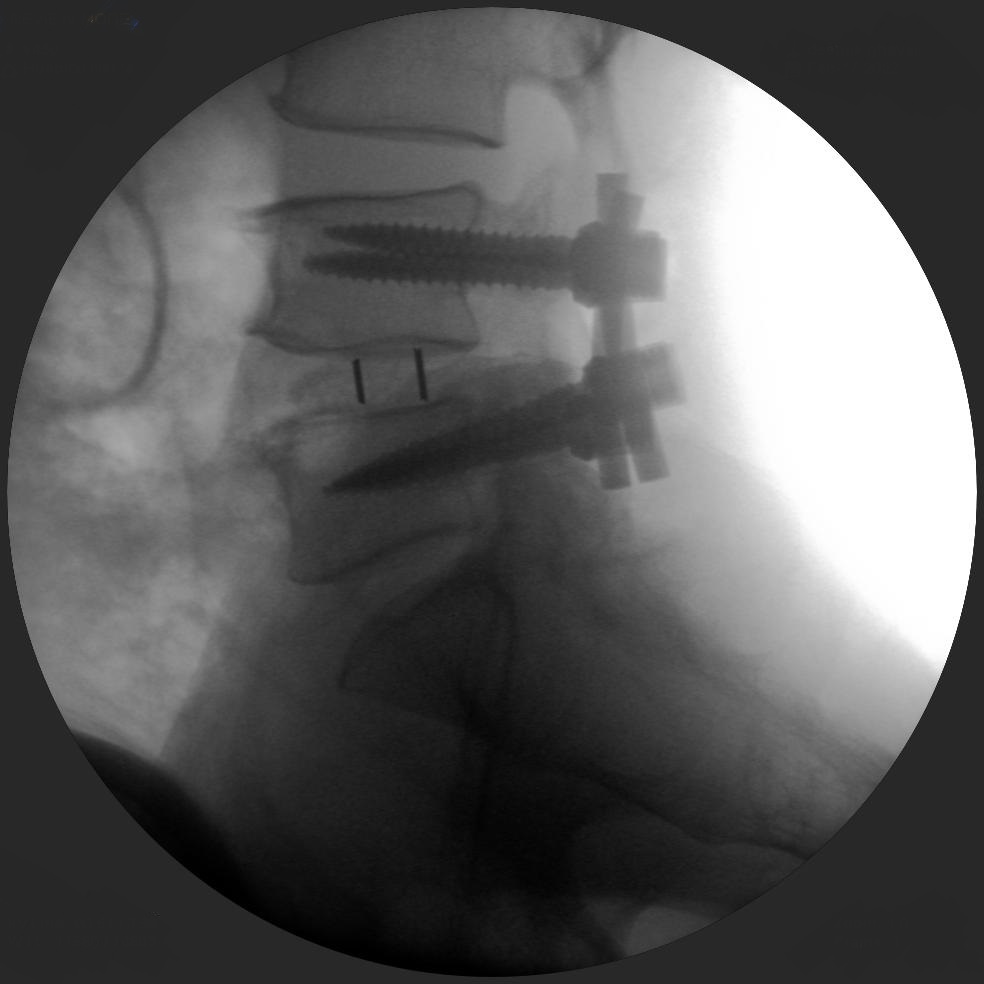

High-quality imaging

Skan-C uses advanced imaging technology, such as pulsed fluoroscopy and digital subtraction angiography, to provide highly detailed images of the affected area. This allows doctors to perform procedures with increased precision and accuracy, and better patient outcome

Clinical Evidence

Skan-C is a great C-arm for neurology treatments for several reasons